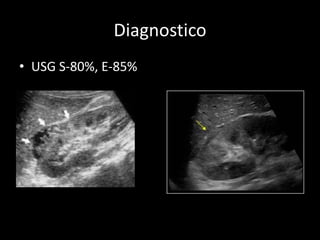

Diagnostico

• USG S-80%, E-85%